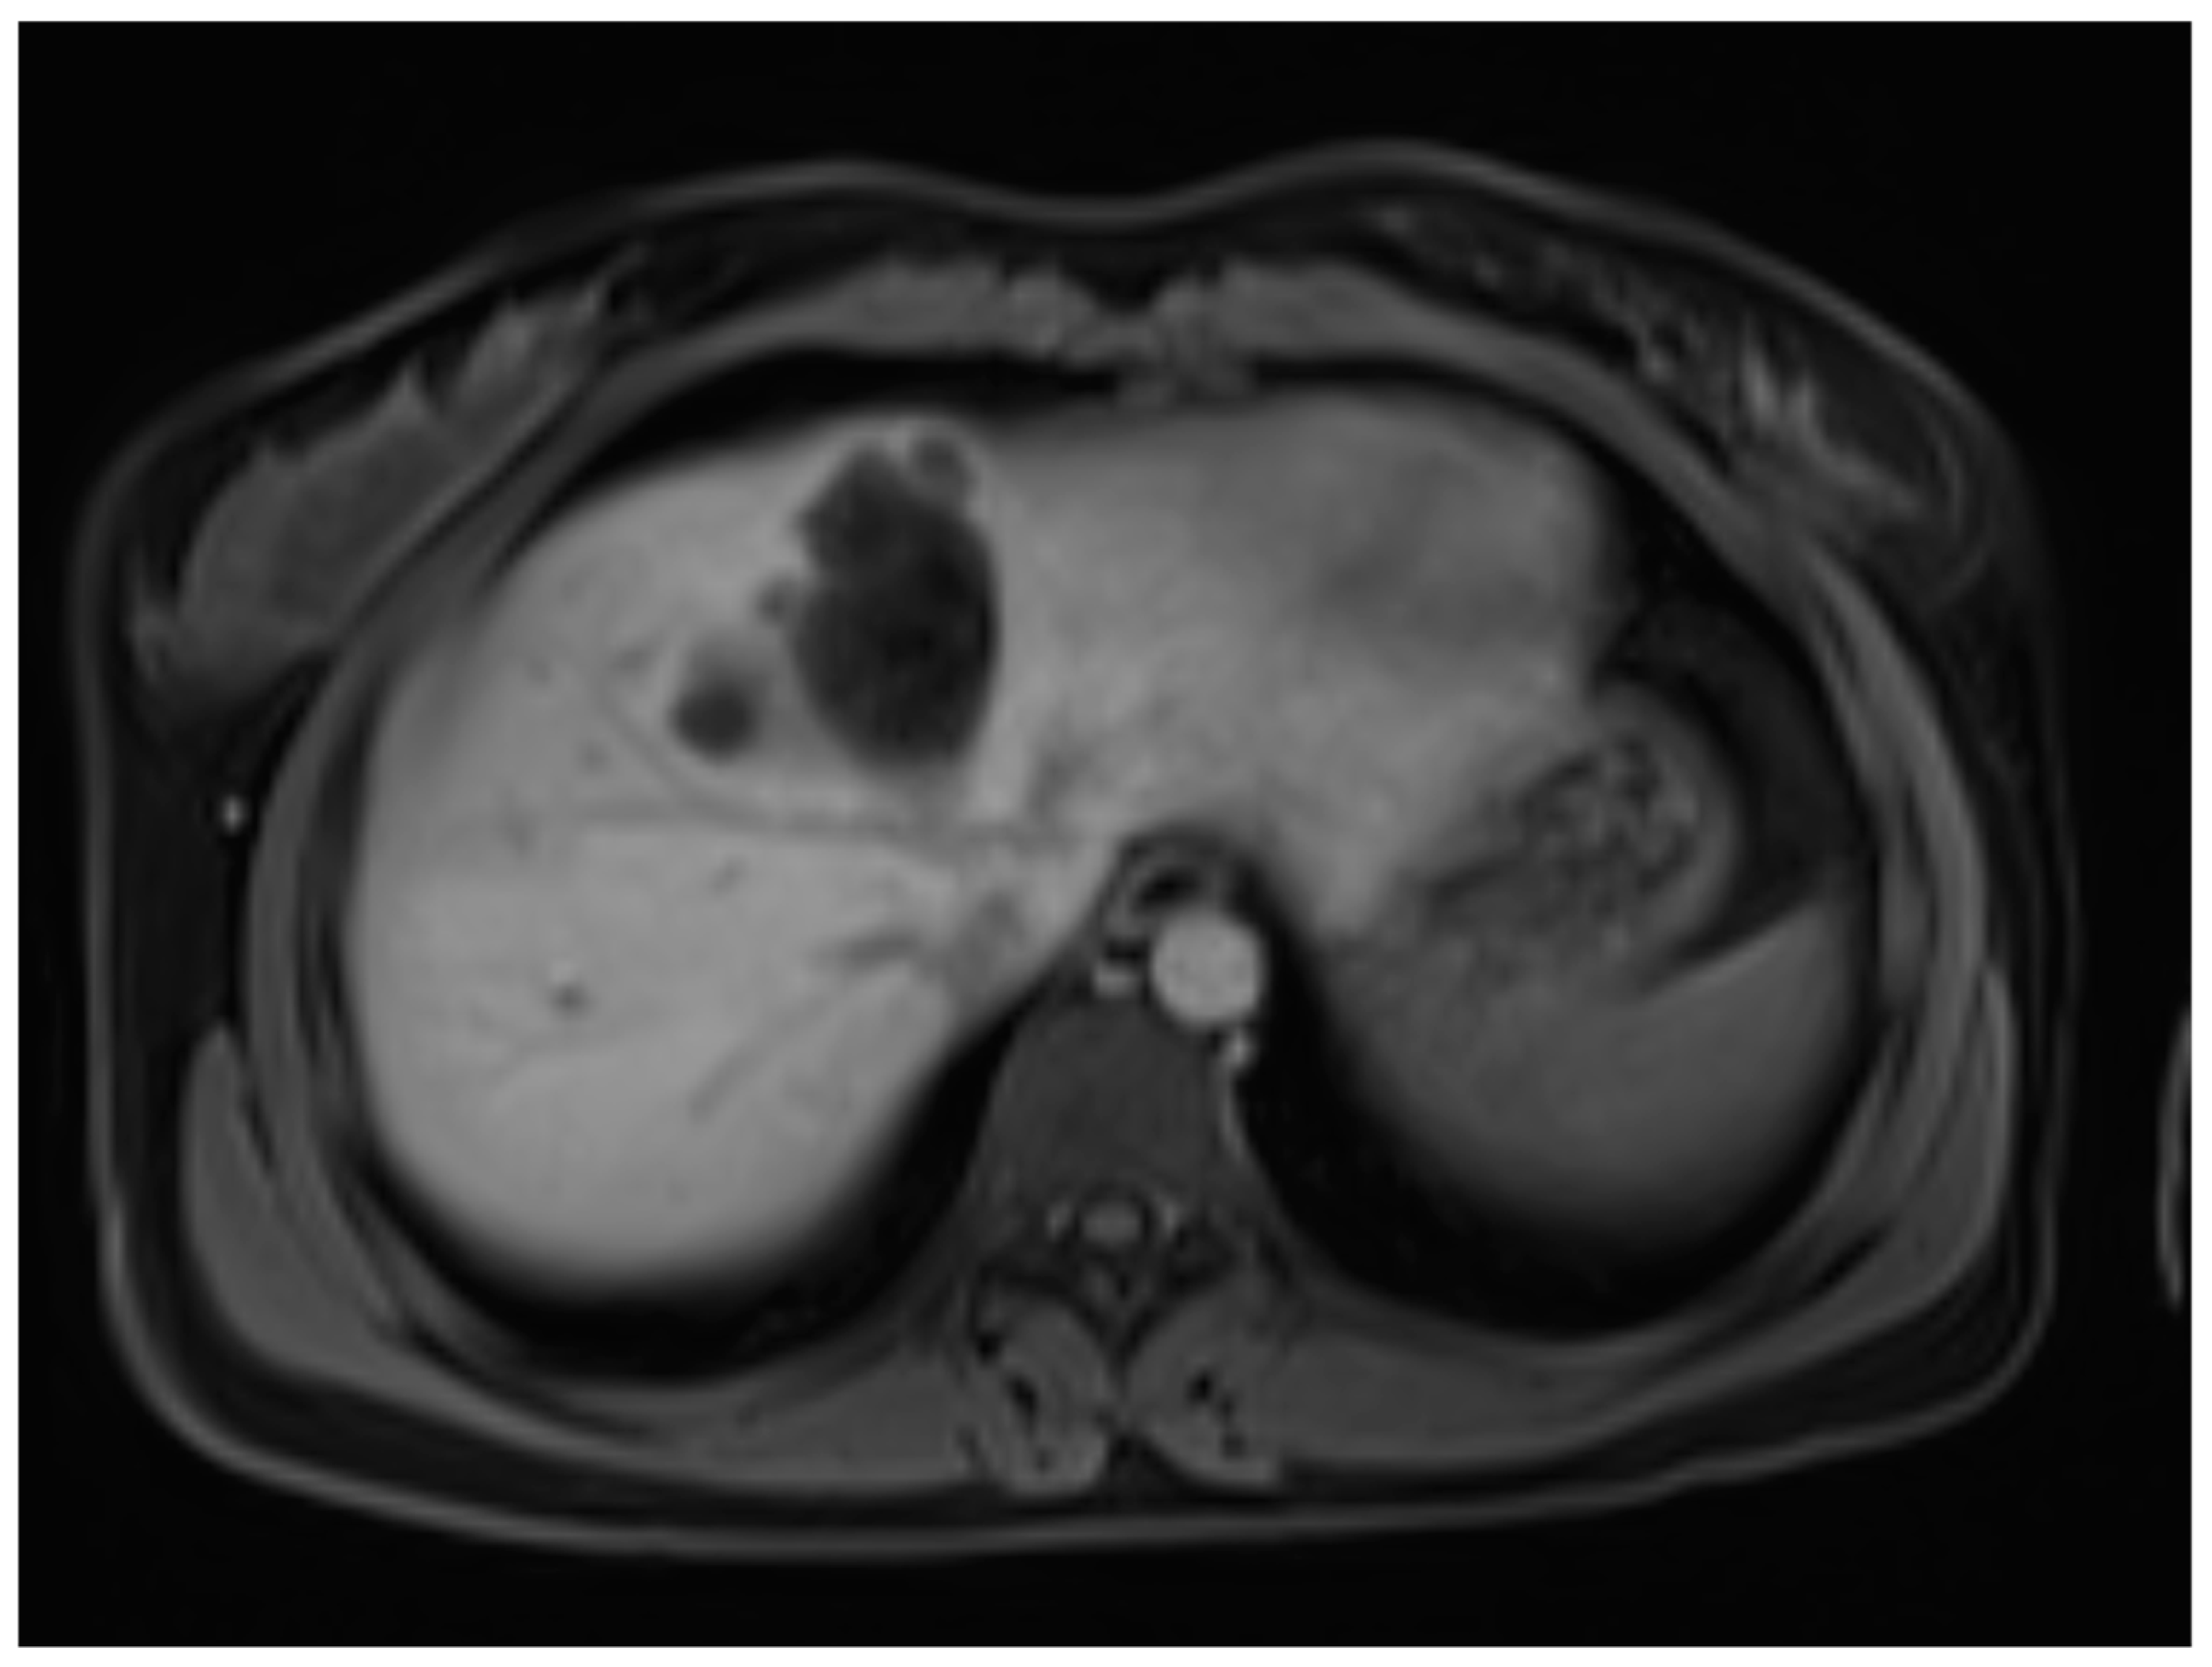

A liver MRI scan confirmed a cystic structure with multiple daughter cysts, hypointense on a T1-weighted image (T1WI), and hyperintense on a T2-weighted image (T2WI), with no solid components, no signs of membrane rupture, and a maximum diameter of 10 cm (craniocaudal) (Figure 1). Additionally, elevated signals on T2WI in the surrounding liver tissue were found. The T1 sequences did not reveal any contrast uptake after 5 (Figure 2), 10, or 20 (Figure 3) minutes post-injection. Furthermore, DWI/ADC mapping indicated a hydatid cyst. The DWI sequences included a trace DWI (Figure 4), an ADC map (Figure 5), and both at b800. Radiomics and AI tools were not involved. The trace DWI showed an area of hypointensity in the region of the cyst that was surrounded by a hypointense layer, depicting the cystic wall. The ADC map revealed hyperintensity within the area, in concordance with a typical depiction of cysts on an MRI scan.

Figure 3.

First MRI scan: Axial T1W MRI scan depicting hypointense areas in liver segment IV, suspicious of daughter cysts, with no contrast uptake after 10 min.

In diagnosing CE, MRI scanning is of more value than CT [16]. On an MRI scan, hepatic cysts show homogeneous very-low signal intensity on T1WI and homogeneous very-high signal intensity on T2WI. Due to its fluid content, there is a notable increase in signal intensity on heavily T2WI, which helps to differentiate these cysts from metastatic lesions [17]. No enhancement is observed after the administration of gadolinium contrast. In rare cases of intracystic hemorrhage, when blood products are mixed within the cyst, the signal intensity becomes high, and a fluid–fluid level is seen both on T1WI and T2WI [15]. These features are observed within hydatid cysts as well, although there are differences regarding their histopathological features. A hydatid cyst has three distinct layers, as follows: the outer adventitial layer formed by the host’s liver tissue (pericyst), the middle laminated layer derived from the parasite, and the inner germinal layer derived from the parasite [7,16].